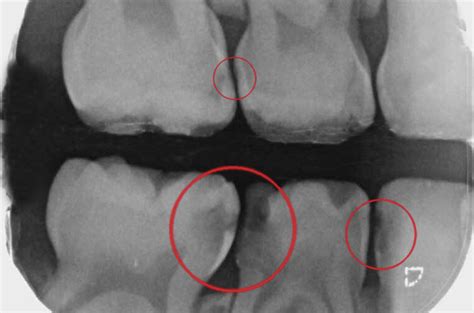

La prueba diagnóstica más adecuada para las caries interproximales será una radiografía oral y una exhaustiva exploración dental.

Las caries interproximales son más difíciles de detectar y, al afectar a más de un diente, son especialmente graves.

Será el especialista quien, mediante una radiografía, pueda hacer un diagnóstico y aplicar el tratamiento para las caries interproximales más adecuado.